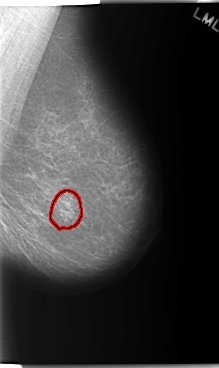

C_0160_1.LEFT_CC

LEFT_CC LINES 5968 PIXELS_PER_LINE 3440 BITS_PER_PIXEL 12 RESOLUTION 50 OVERLAY

FILE: C_0160_1.LEFT_CC.OVERLAY

TOTAL_ABNORMALITIES 1

ABNORMALITY 1

LESION_TYPE MASS SHAPE OVAL MARGINS MICROLOBULATED

ASSESSMENT 4

SUBTLETY 4

PATHOLOGY MALIGNANT

TOTAL_OUTLINES 1

BOUNDARY